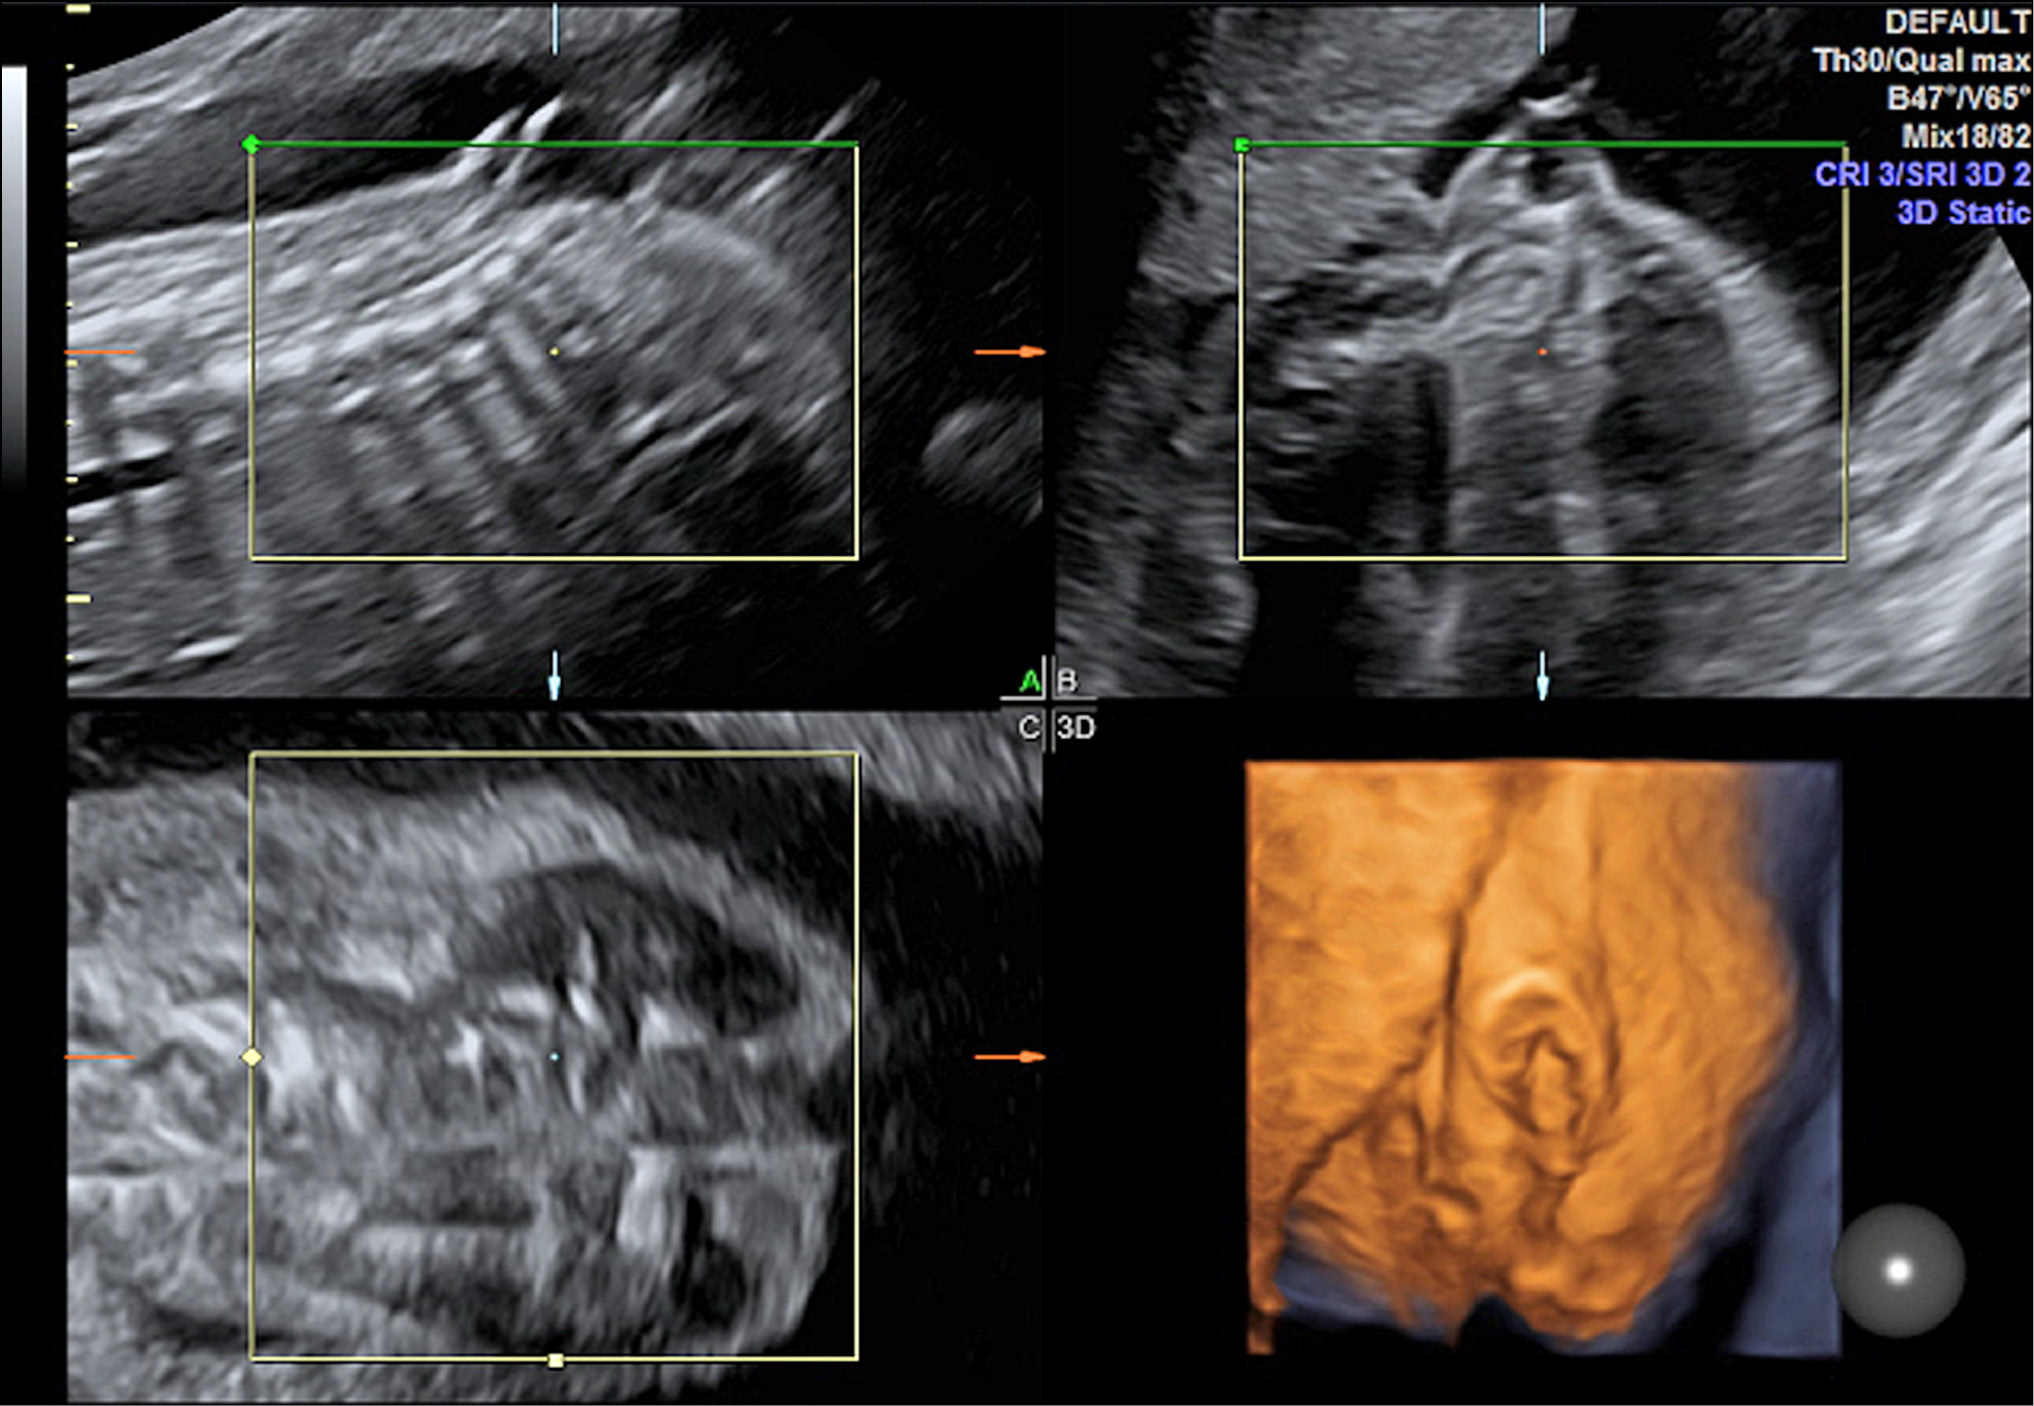

Рис. 3. Эхограмма 3D/4D. Режим мультиплановый. Беременность 16 нед. Подтвержденный врожденный порок развития плода. Двусторонняя внутренняя гидроцефалия. Маловодие. А, B, С — три взаимно перпендикулярные плоскости изображений головного мозга плода. D — поверхностный режим

Fig. 3. Echogram 3D / 4D. Multi-plan mode. Pregnancy 16 weeks Confirmed congenital malformation of the fetus. Bilateral internal hydrocephalus. Low water. A, B, C - three mutually perpendicular planes of images of the fetal brain. D - surface mode

Рис. 4. Эхограмма 3D/4D. Режим мультиплановый. Беременность 23 нед. Подтвержденный врожденный порок развития плода. Spina bifida (сакральный отдел). Менингомиелоцеле. Маловодие. А, B, С — три взаимно перпендикулярные плоскости изображений позвоночника плода и менингомиелоцеле. D — поверхностный режим

Fig. 4. Echogram 3D / 4D. Multi-plan mode. Pregnancy 23 weeks. Confirmed congenital malformation of the fetus. Spina bifida (sacral department). Meningomyelocele. Low water. A, B, C - three mutually perpendicular planes of images of the fetal spine and meningomyelocele. D - surface mode